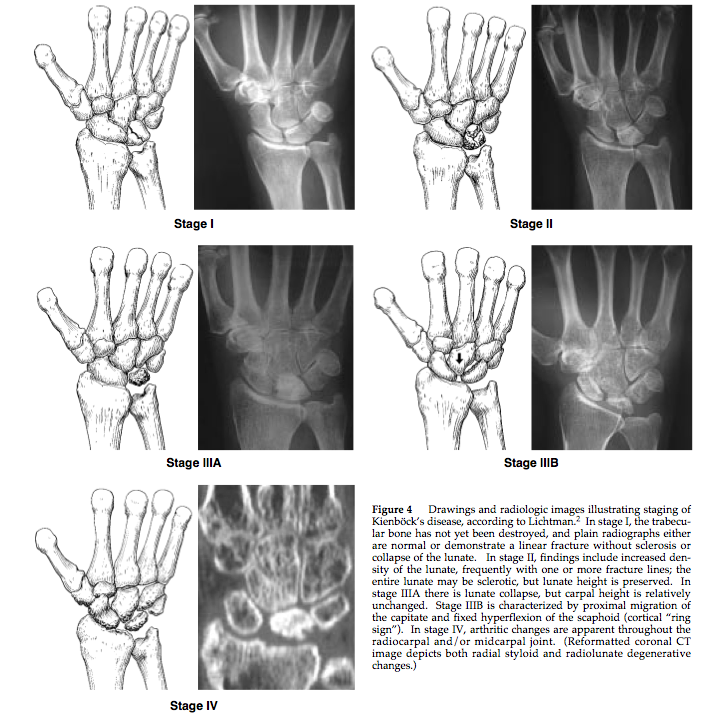

Diagnosis? Classification

Keinboch’s - Litchman Classification

Imaging to help define collapse of lunate